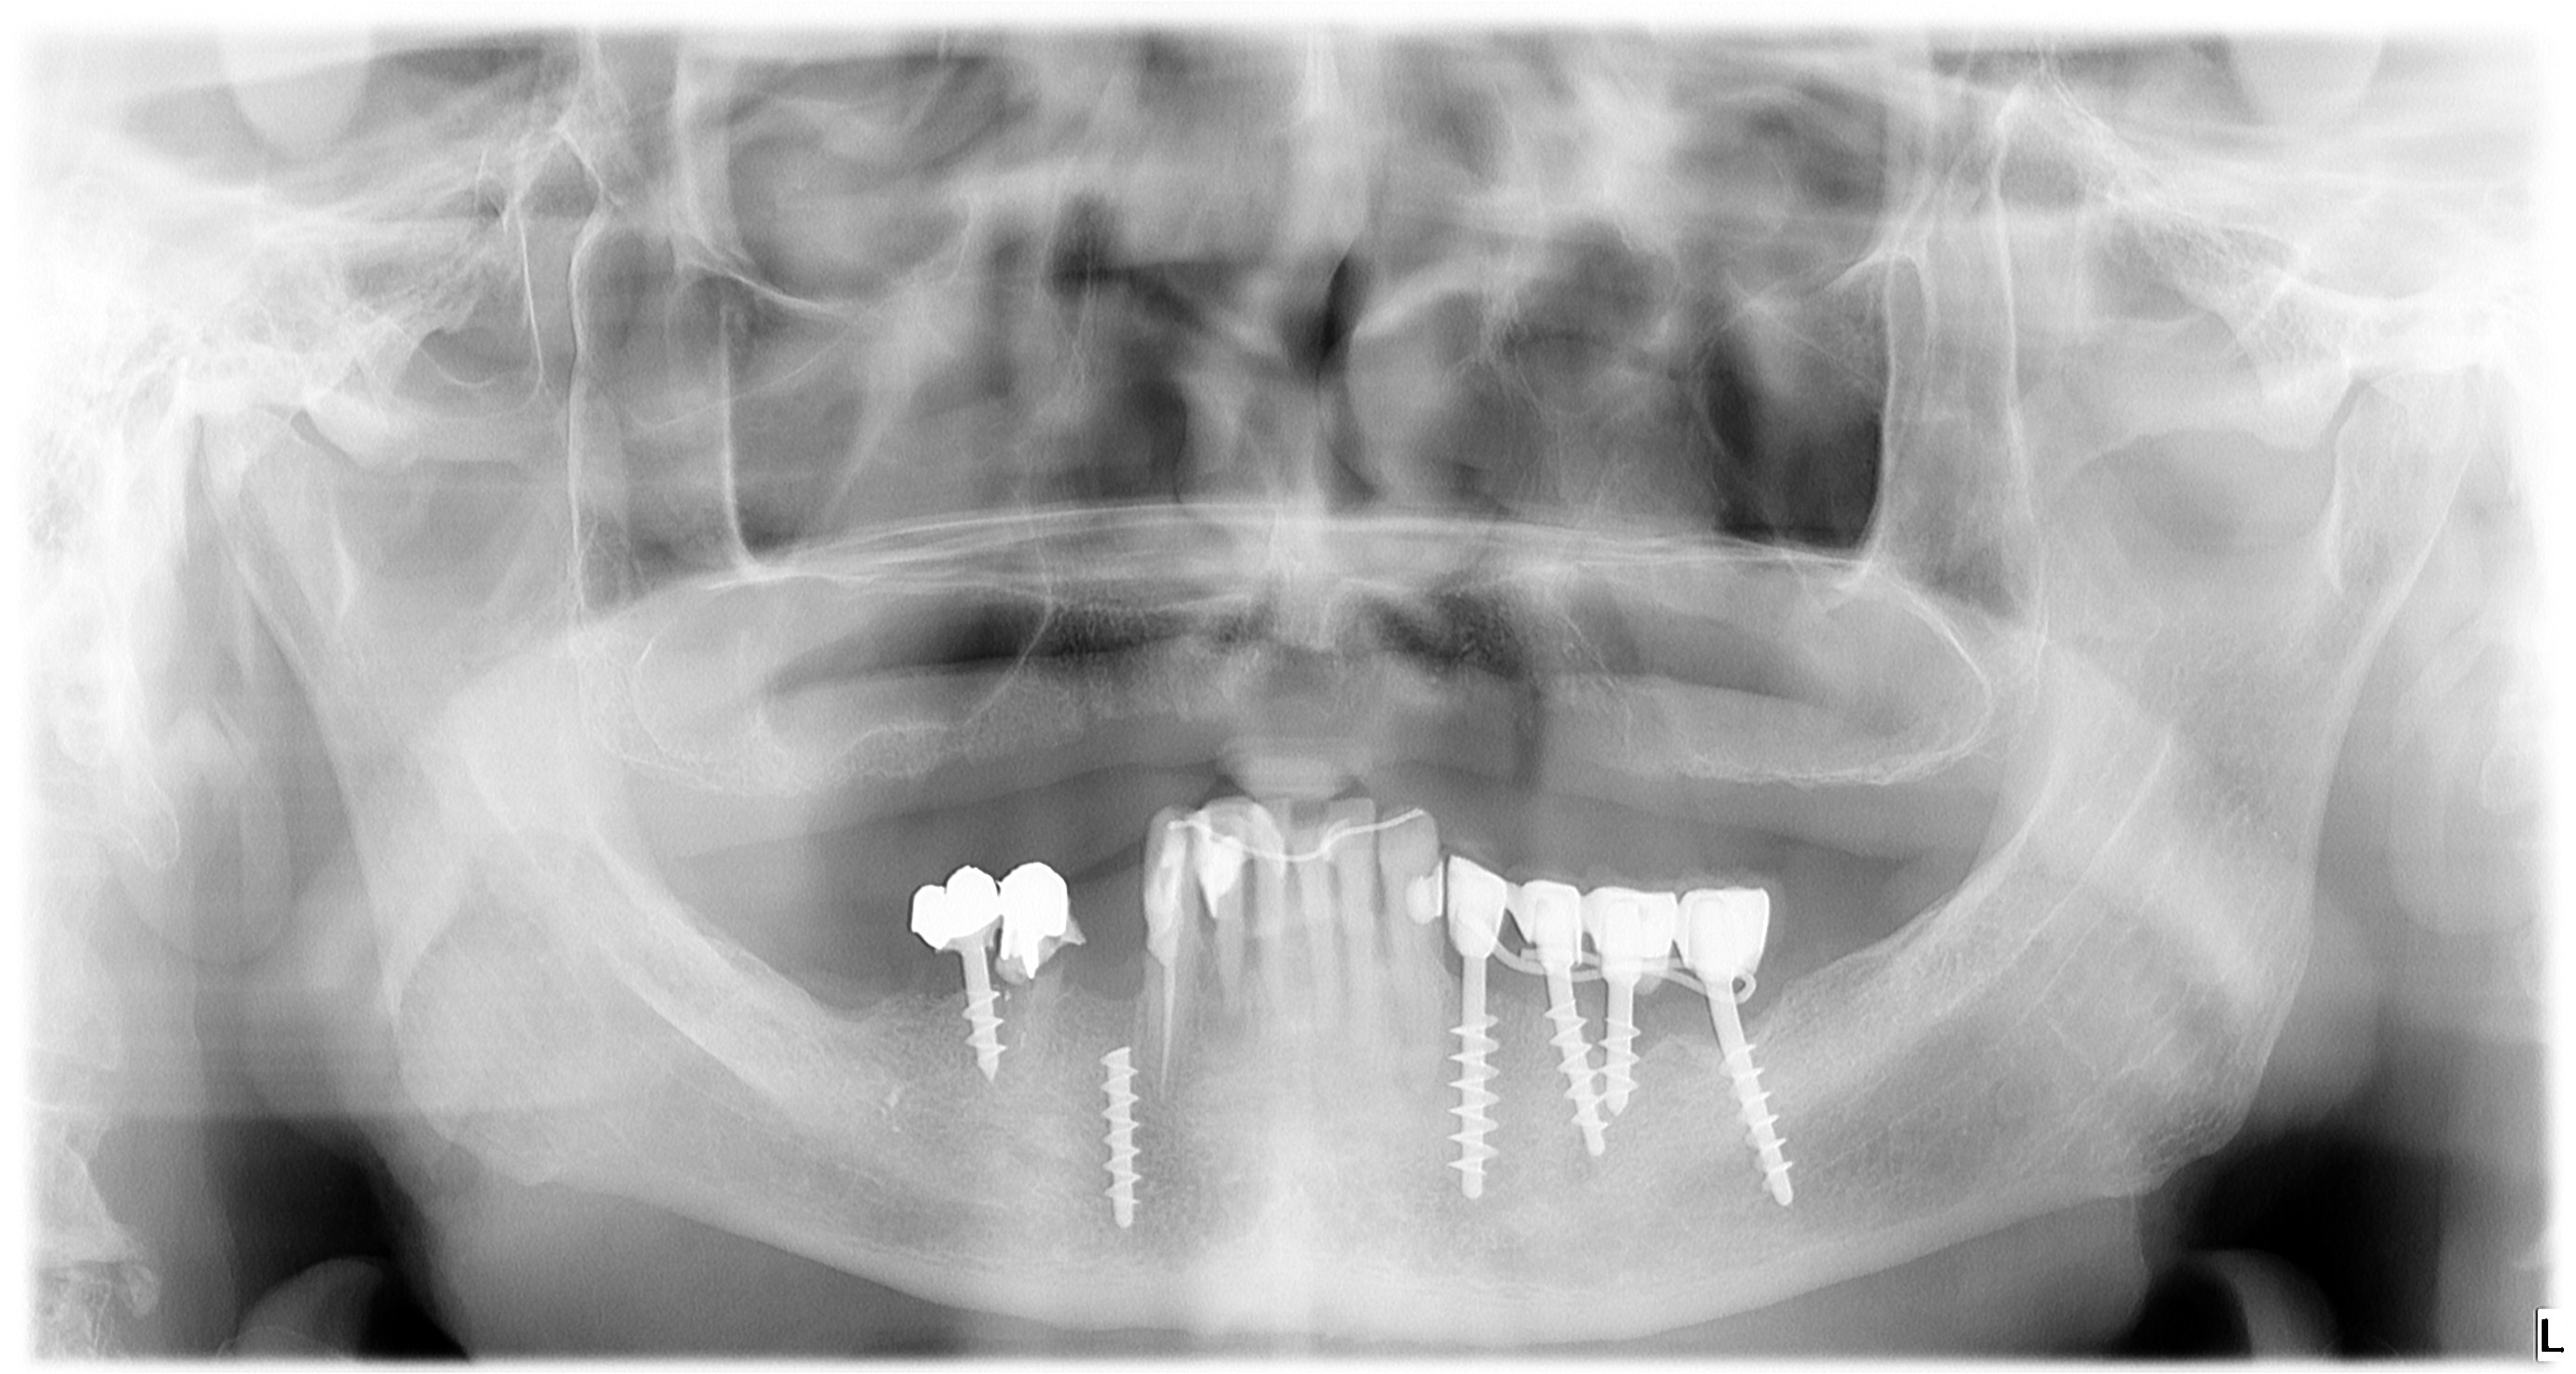

Nella radiografia seguente

si notano: in 6- e -6 due impianti di Tramonte risalenti a circa 40 anni fa (il paz. ne ha perso il ricordo esatto), in -7 un impianto Tramonte "crociante" (si dicono crocianti gli impianti che incrociano il NAI per linguale o per vestibolare), e infine, il problema, un impianto spezzato in posizione 4-. In posizione 65- residua una vecchia protesi in oro e resina, probabilmente risalente all'epoca dell'inserimento implantare, il cui rivestimento estetico è completamente scomparso insieme alla corona di 5-. Il paziente, che ha 81 anni e soffre di una grave forma tumorale, vorrebbe evitare di sottoporsi ad un intervento di estrazione del residuo implantare profondamente infisso in 4- ma patisce l'inefficienza masticatoria di destra e vuole essere riabilitato.Si opta, dunque, per un inserimento appena distale, ma con un piccolo trucco per evitare l'eccessiva distalizzazione del moncone. Il piano di lavoro prevede, dunque, l'estrazione del moncone radicolare in 5- ed un impianto postestrattivo e l'inserimento di un secondo impianto in posizione 4-. Ma in posizione 4- l'inserimento non è possibile, dato il permanere dell'ingombro della porzione endossea dell'impianto fratturato. Si potrebbe inserire distalmente ma così il moncone dell'impianto sostitutivo del 4- verrebbe a trovarsi troppo vicino a quello del postestrattivo in 5-, con conseguenti problemi protesici (spaziatura incongrua) in una zona di un qualche interesse estetico. In questi casi, Garbaccio si rivela la soluzione più efficace semplice e pratica possibile. La sua punta aguzza evita facilmente il residuo fratturato e se anche lo impattasse, gli scivolerebbe di lato trovandosi una strada facilmente con un minimo di guida usando la chiave a cacciavite lunga. Un impianto Tramonte standard non ci riuscirebbe tanto facilmente né in maniera così pulita, ma soprattutto non riuscirebbe a tenersi così accostato poiché si bloccherebbe contro il residuo in inclusione. Poter inserire come si vede in radiografia sfiorando il corpo dell'impianto fratturato, ci permette di ottenere per il moncone una corretta posizione protesica. Il tuttoin maniera facile, semplice, atraumatica, veloce e senza lembo.